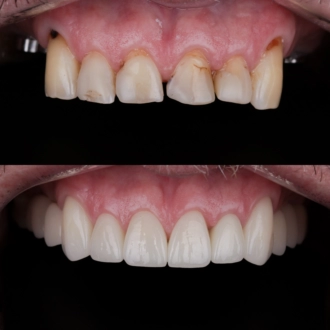

Процедура имплантации — это быстрый, современный и безопасный метод восстановления архитектуры улыбки. Еще 10 лет назад с процедурой ассоциировалось множество предубеждений и опасений. Но сегодня в арсенале врачей есть большая подборка атравматичных методик, материалов и методов реабилитации, которые делают имплантацию абсолютно рутинной процедурой. В сети стоматологий РЕФЕРТА процедура имплантации выполняется по современным протоколам с использованием премиальных материалов. Вы можете быть уверены в исключительной безопасности выполнения и сияющем результате процедуры.

При немедленной одноэтапной процедуре имплантат устанавливается в кость сразу после удаления зуба, а на абатмент имплантата устанавливается временная коронка. Временная коронка заменяется на фарфоровую коронку после периода полного приживления имплантата. Этот вариант процедуры является менее травматичным для костной ткани и имеет значительно меньший период восстановления. Врачи РЕФЕРТА в совершенстве владеют этой методикой, благодаря чему наши пациенты значительно сокращают свой путь к заветной улыбке.